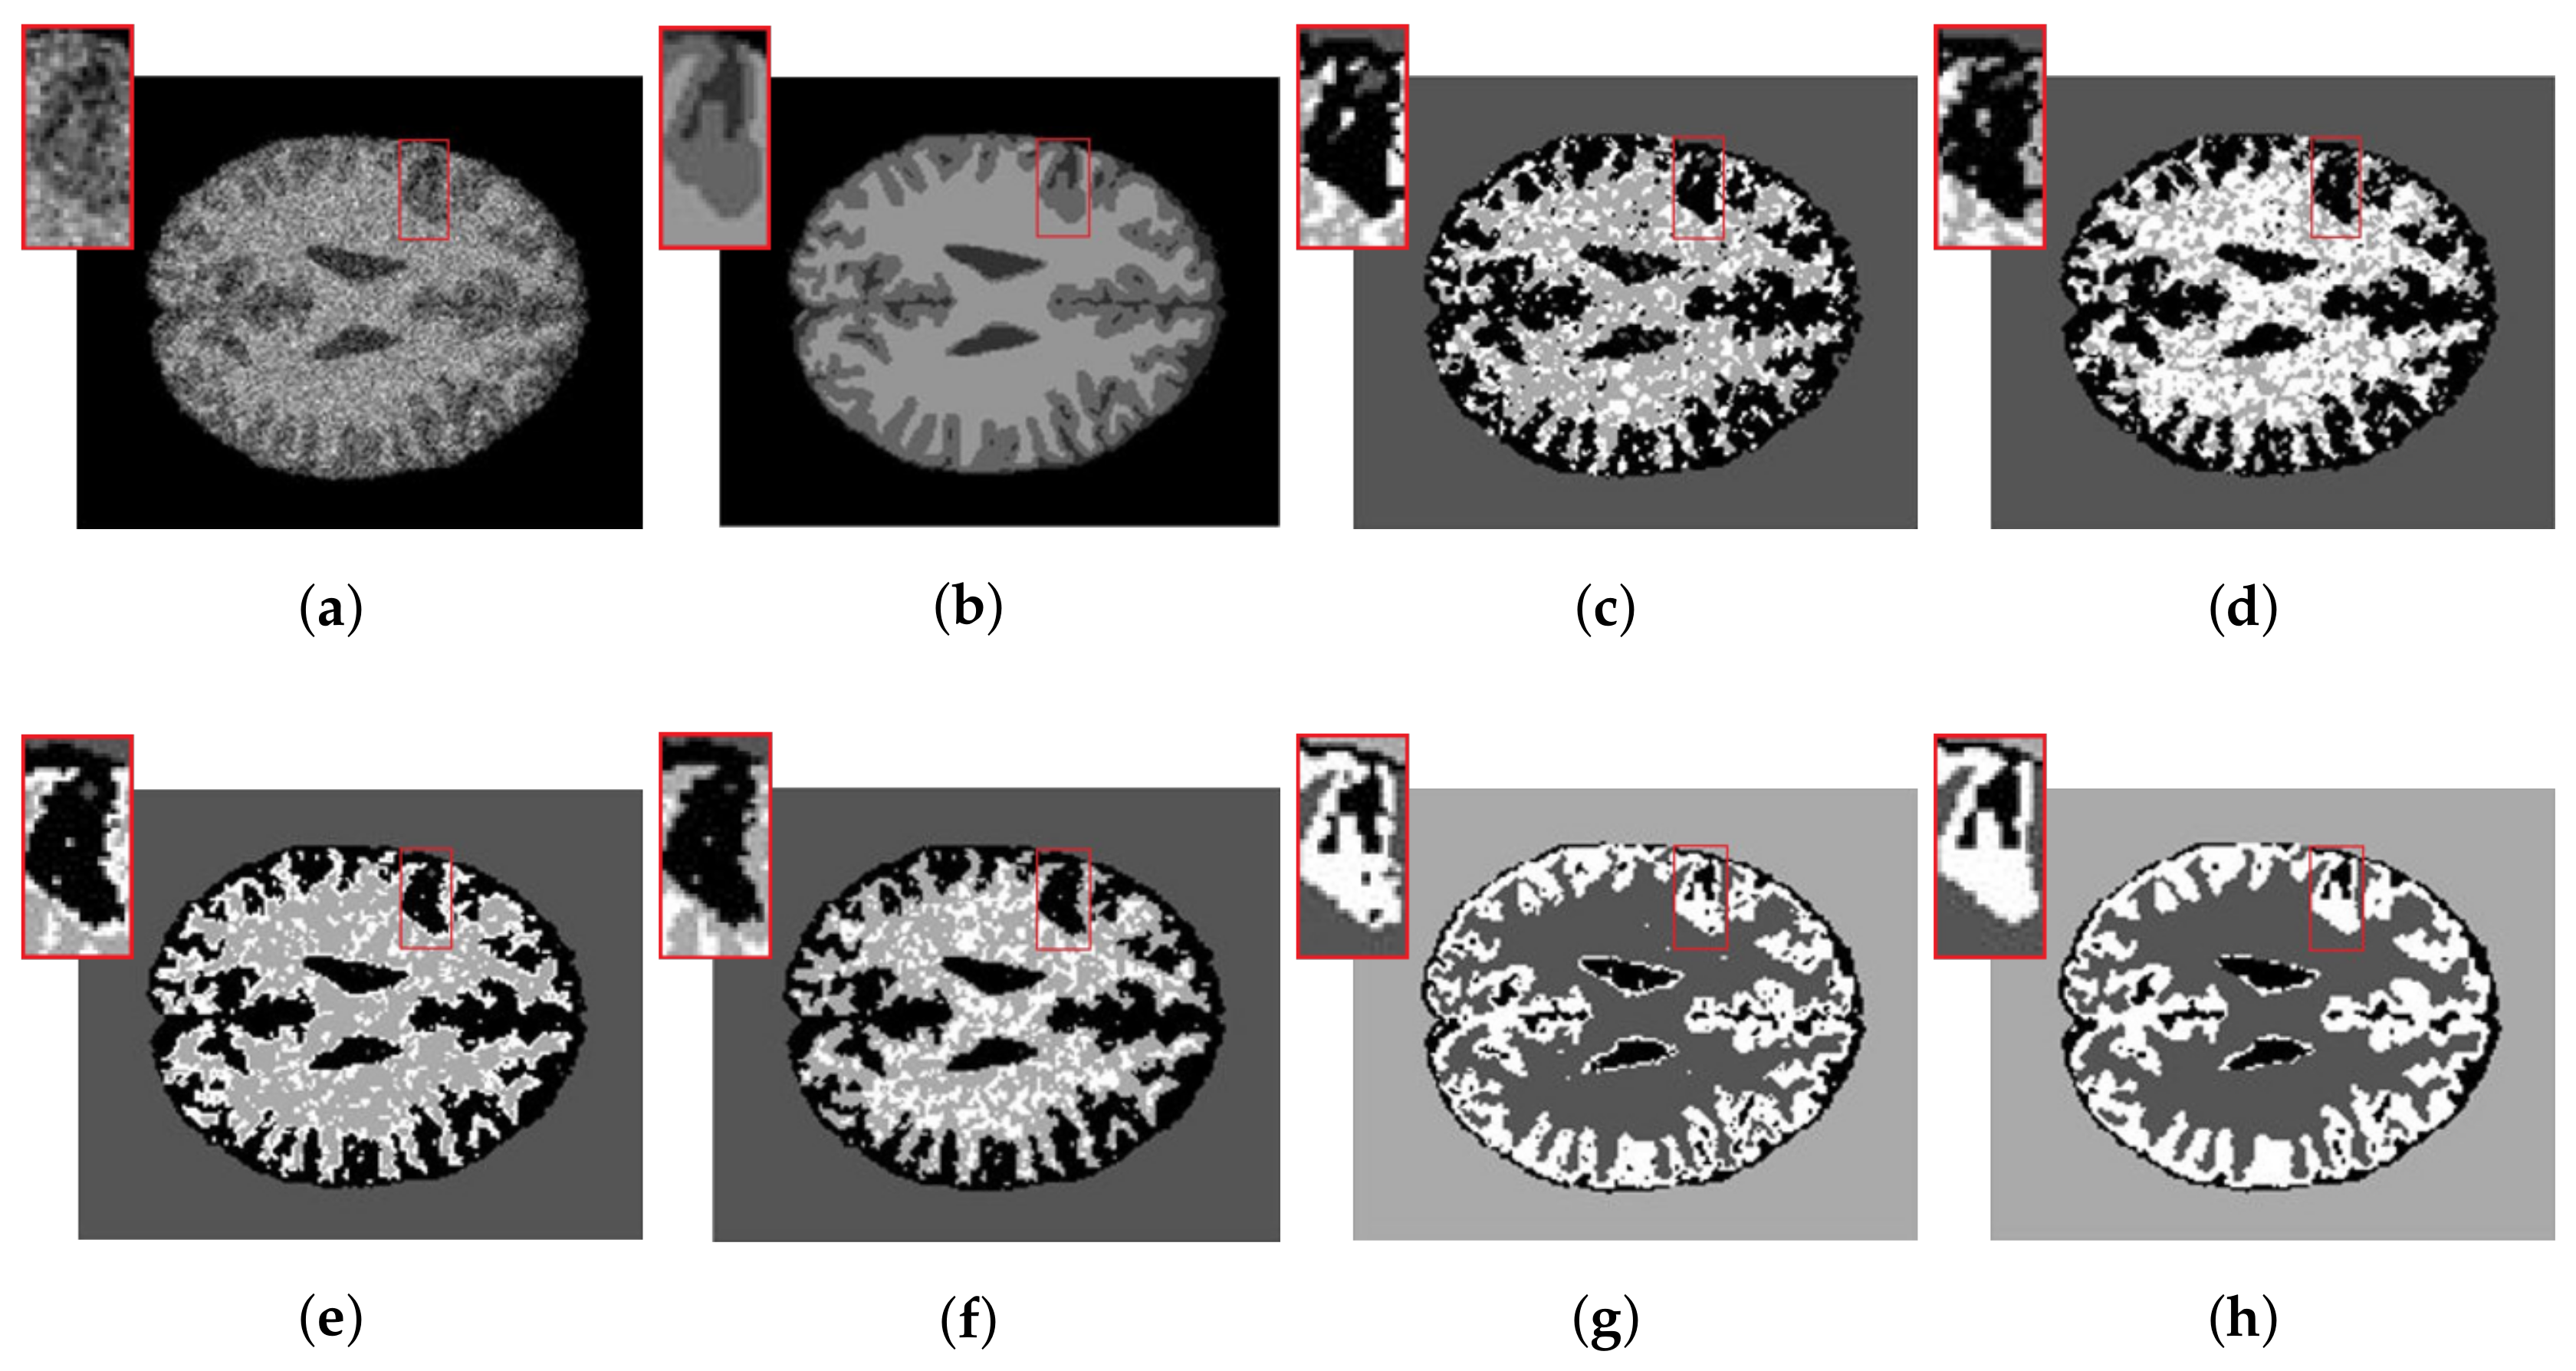

4.2. Real Images